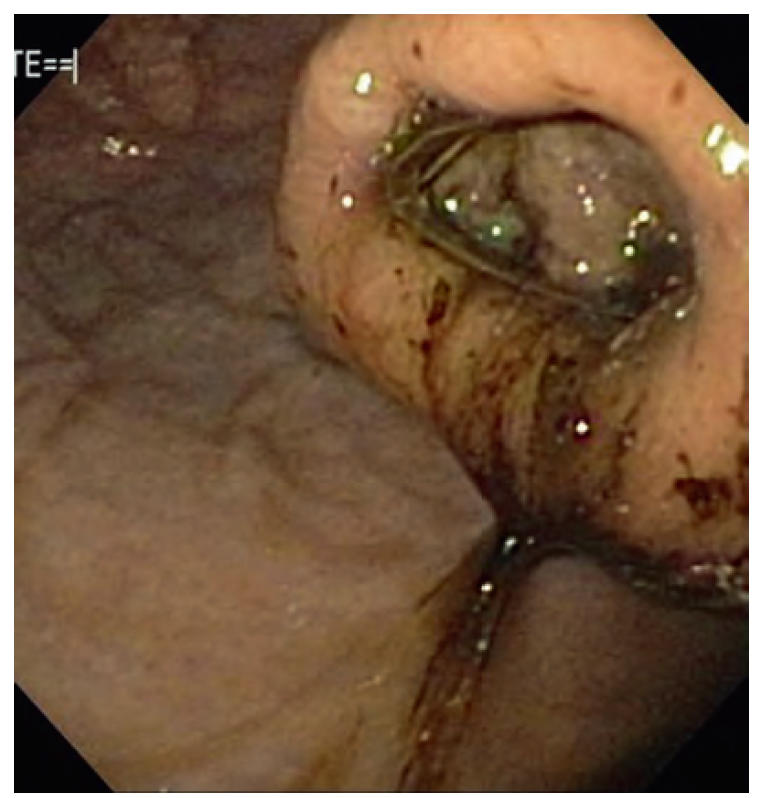

- 内镜是GUE最敏感的方法(图1),但胃内容物(大量血液及血块;图2)可掩盖病变。内镜可取材活检。溃疡边缘活检困难且价值有限,通常取溃疡基底及周围正常组织更易且信息量相当;慎取溃疡中心,极少致穿孔。若内镜活检致穿孔,该溃疡迟早也会自发穿孔。

图1. 溃疡性肿瘤:下食管括约肌处可见溃疡性平滑肌瘤。